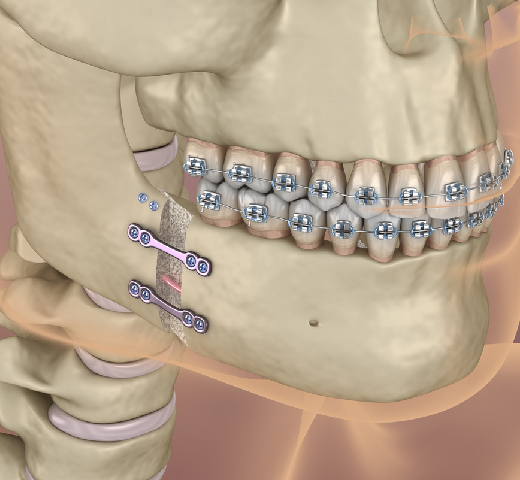

Surgery may involve the use of plates, screws, and wires to secure the bones in the correct position. Post-treatment care includes a soft or liquid diet, pain management, and possibly antibiotics to prevent infection. Rehabilitation exercises may be necessary to restore full jaw function over time.

Treatment options range from non-surgical methods, like wiring the jaws shut for minor fractures, to surgical interventions using plates, screws, and wires to secure the bones for more severe fractures.